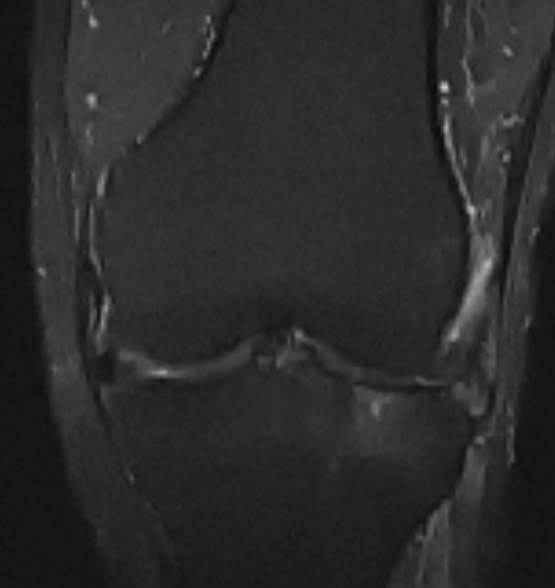

Собственно на качество влияет мощность томографа от 0,5 до 3 тесла. А так же наличие специальных катушек для каждой зоны. В интернете можно найти МРТ томографы открытого типа, но они имеют самое низкое качество визуализации, где можно увидеть только самые явные патологические изменения.

1,5 Тесла

3 Тесла

Вердикт. Чем больше мощность, тем лучше качество исследования, необходима нужная катушка, диск наиболее информативен.